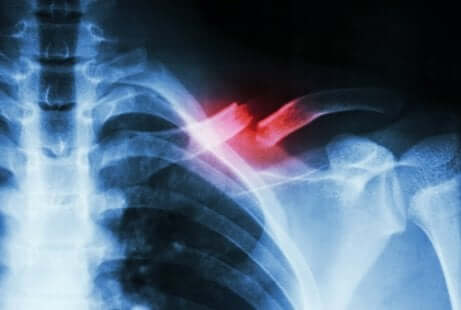

Diese Art von Fraktur ist nicht einfach zu diagnostizieren. Sie erfordert einen Spezialisten und ergänzende Tests, um sie nicht mit einer anderen Pathologie zu verwechseln. Das liegt daran, dass eine Fraktur dieser Art normalerweise nicht auf einem gewöhnlichen Röntgenbild erkannt werden kann.

Ein Ermüdungsbruch ist eine Art Riss im Knochen. Dieser ist auf wiederholte Mikrotraumata oder eine Überlastung zurückzuführen. Er manifestiert sich durch starke Schmerzen, die bei körperlicher Aktivität auftreten und wieder verschwinden, sobald man damit aufhört.